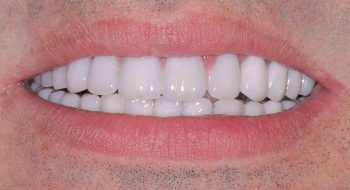

Tooth implant procedure (Dental implant procedure)?

Tooth implant surgery is a procedure that replaces missing tooth or damaged tooth with screw like bio-compatible material called titanium or zirconium. The damaged tooth is removed and the tooth implant is placed in the jaw bone under anaesthesia by an implantologist. Once the tooth implant is placed in the jaw bone, it is allowed to heal and osseointegrate (fuse with the surrounding bone) to become part of the human body. After 4-6 months’ time, the crown is placed on the implant to restore the functionality of the tooth.